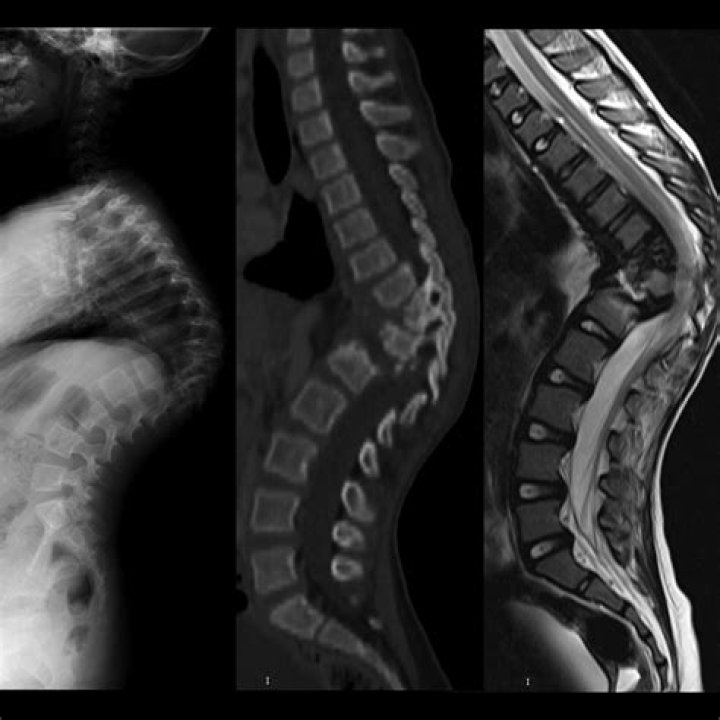

What is TB osteomyelitis?

Tuberculous osteomyelitis is an uncommon infection that usually involves the vertebrae. An otherwise healthy young man with a chronic discharging sinus on his right foot caused by tuberculous osteomyelitis is described.